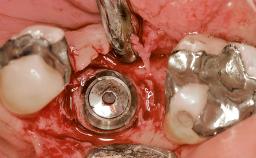

Early Placement of an Implant in a Maxillary Right Central Incisor Site

Bone Augmentation Horizontal|Simultaneous

Augmentation Materials Autogenous chips|Xenogenous|Membrane

Bone Volume Deficient horizontally, allowing simultaneous augumentation